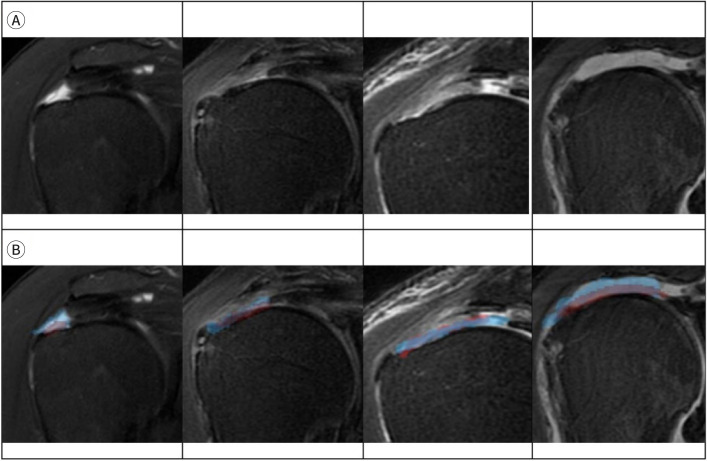

肩部疾病对老年人构成了重大的健康挑战,通常会导致疼痛、功能衰退和独立性下降。本文探讨了深度学习(DL)如何通过自动化任务(如图像分割、疾病检测和运动分析)来解决诊断挑战。最近的研究强调了基于dl的卷积神经网络和机器学习框架在诊断各种肩部病变方面的有效性。自动图像分析有助于在MRI或CT扫描中准确评估肩袖撕裂大小,肌肉变性和脂肪浸润,经常匹配或超过人类专家的准确性。基于卷积神经网络的系统还擅长对骨折和关节状况进行分类,能够从x线平片中快速识别肩部疼痛的常见原因。此外,姿势估计等先进技术提供了肩关节活动范围的精确测量,并支持个性化的康复计划。这些自动化方法在量化局部骨质疏松症方面也取得了成功,利用机器学习衍生的指标对骨密度状态进行分类。DL在提高老年患者肩关节疾病的诊断准确性、效率和一致性方面具有显著的潜力。基于机器学习的成像数据和运动参数评估可以帮助临床医生优化治疗计划并改善患者的预后。然而,为了确保它们的普遍性、可重复性和有效地整合到常规临床工作流程中,大规模的前瞻性验证研究是必要的。随着数据可用性和计算资源的增加,dl驱动应用程序的持续发展有望进一步推进和个性化肌肉骨骼护理,使医疗保健提供者和老龄化人口都受益。

Shoulder diseases pose a significant health challenge for older adults, often causing pain, functional decline, and decreased independence. This narrative review explores how deep learning (DL) can address diagnostic challenges by automating tasks such as image segmentation, disease detection, and motion analysis. Recent research highlights the effectiveness of DL-based convolutional neural networks and machine learning frameworks in diagnosing various shoulder pathologies. Automated image analysis facilitates the accurate assessment of rotator cuff tear size, muscle degeneration, and fatty infiltration in MRI or CT scans, frequently matching or surpassing the accuracy of human experts. Convolutional neural network-based systems are also adept at classifying fractures and joint conditions, enabling the rapid identification of common causes of shoulder pain from plain radiographs. Furthermore, advanced techniques like pose estimation provide precise measurements of the shoulder joint's range of motion and support personalized rehabilitation plans. These automated approaches have also been successful in quantifying local osteoporosis, utilizing machine learning-derived indices to classify bone density status. DL has demonstrated significant potential to improve diagnostic accuracy, efficiency, and consistency in the management of shoulder diseases in older patients. Machine learning-based assessments of imaging data and motion parameters can help clinicians optimize treatment plans and improve patient outcomes. However, to ensure their generalizability, reproducibility, and effective integration into routine clinical workflows, large-scale, prospective validation studies are necessary. As data availability and computational resources increase, the ongoing development of DL-driven applications is expected to further advance and personalize musculoskeletal care, benefiting both healthcare providers and the aging population.